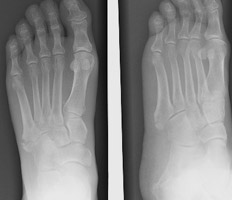

- Click on the image for a larger versionCAP and oblique radiographs of the foot. In contradistinction, this patient sustained a fracture of the proximal aspect of the fifth metatarsal. Greenspan terms this an avulsion injury.